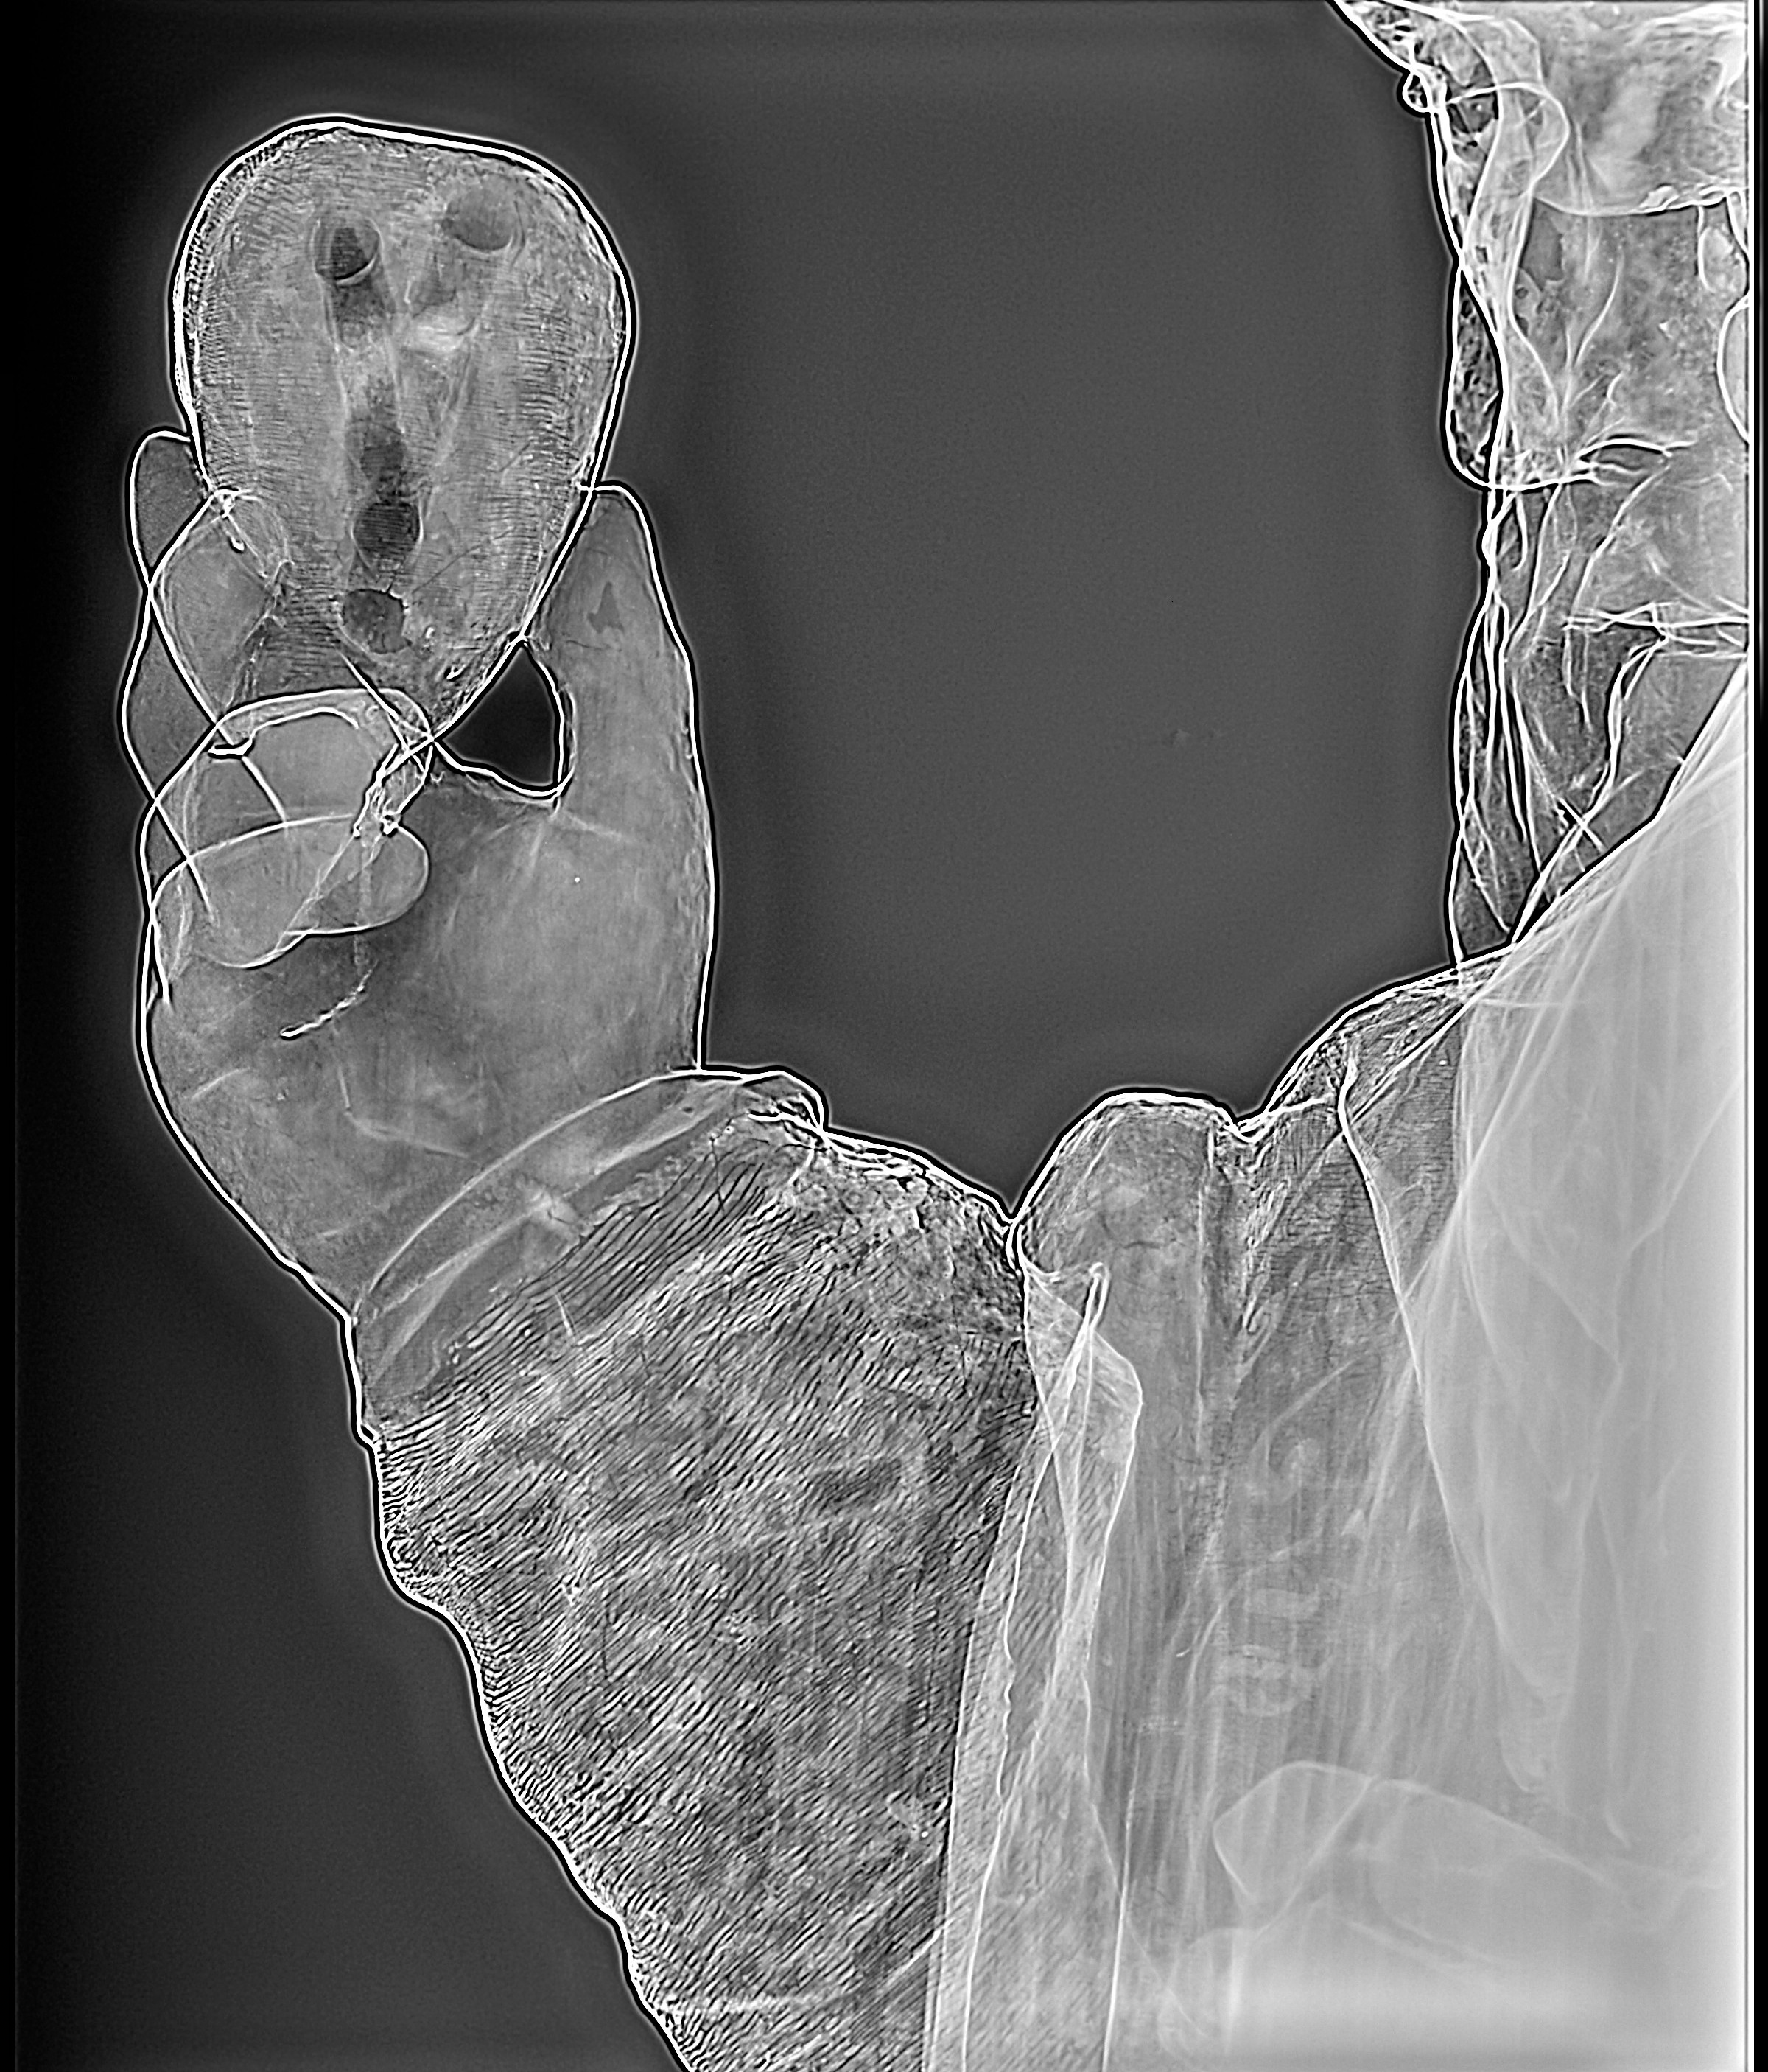

Radiología Digital como Herramienta Complementaria en el Dictamen de Bienes Muebles

Desde el descubrimiento de los rayos “X” y las placas radiográficas por Wilhelm Conrad Roentgen y su posterior difusión a través de la Asociación Físico médica de Wurzburg el 28 de diciembre de 1895, que fue la primera asociación que habló de los nuevos rayos que podían penetrar el cuerpo y fotografiar los huesos, ha habido muchos cambios tanto en la forma de obtener, procesar e incluso en la forma de visualizar, manejar y almacenar las placas radiográficas.